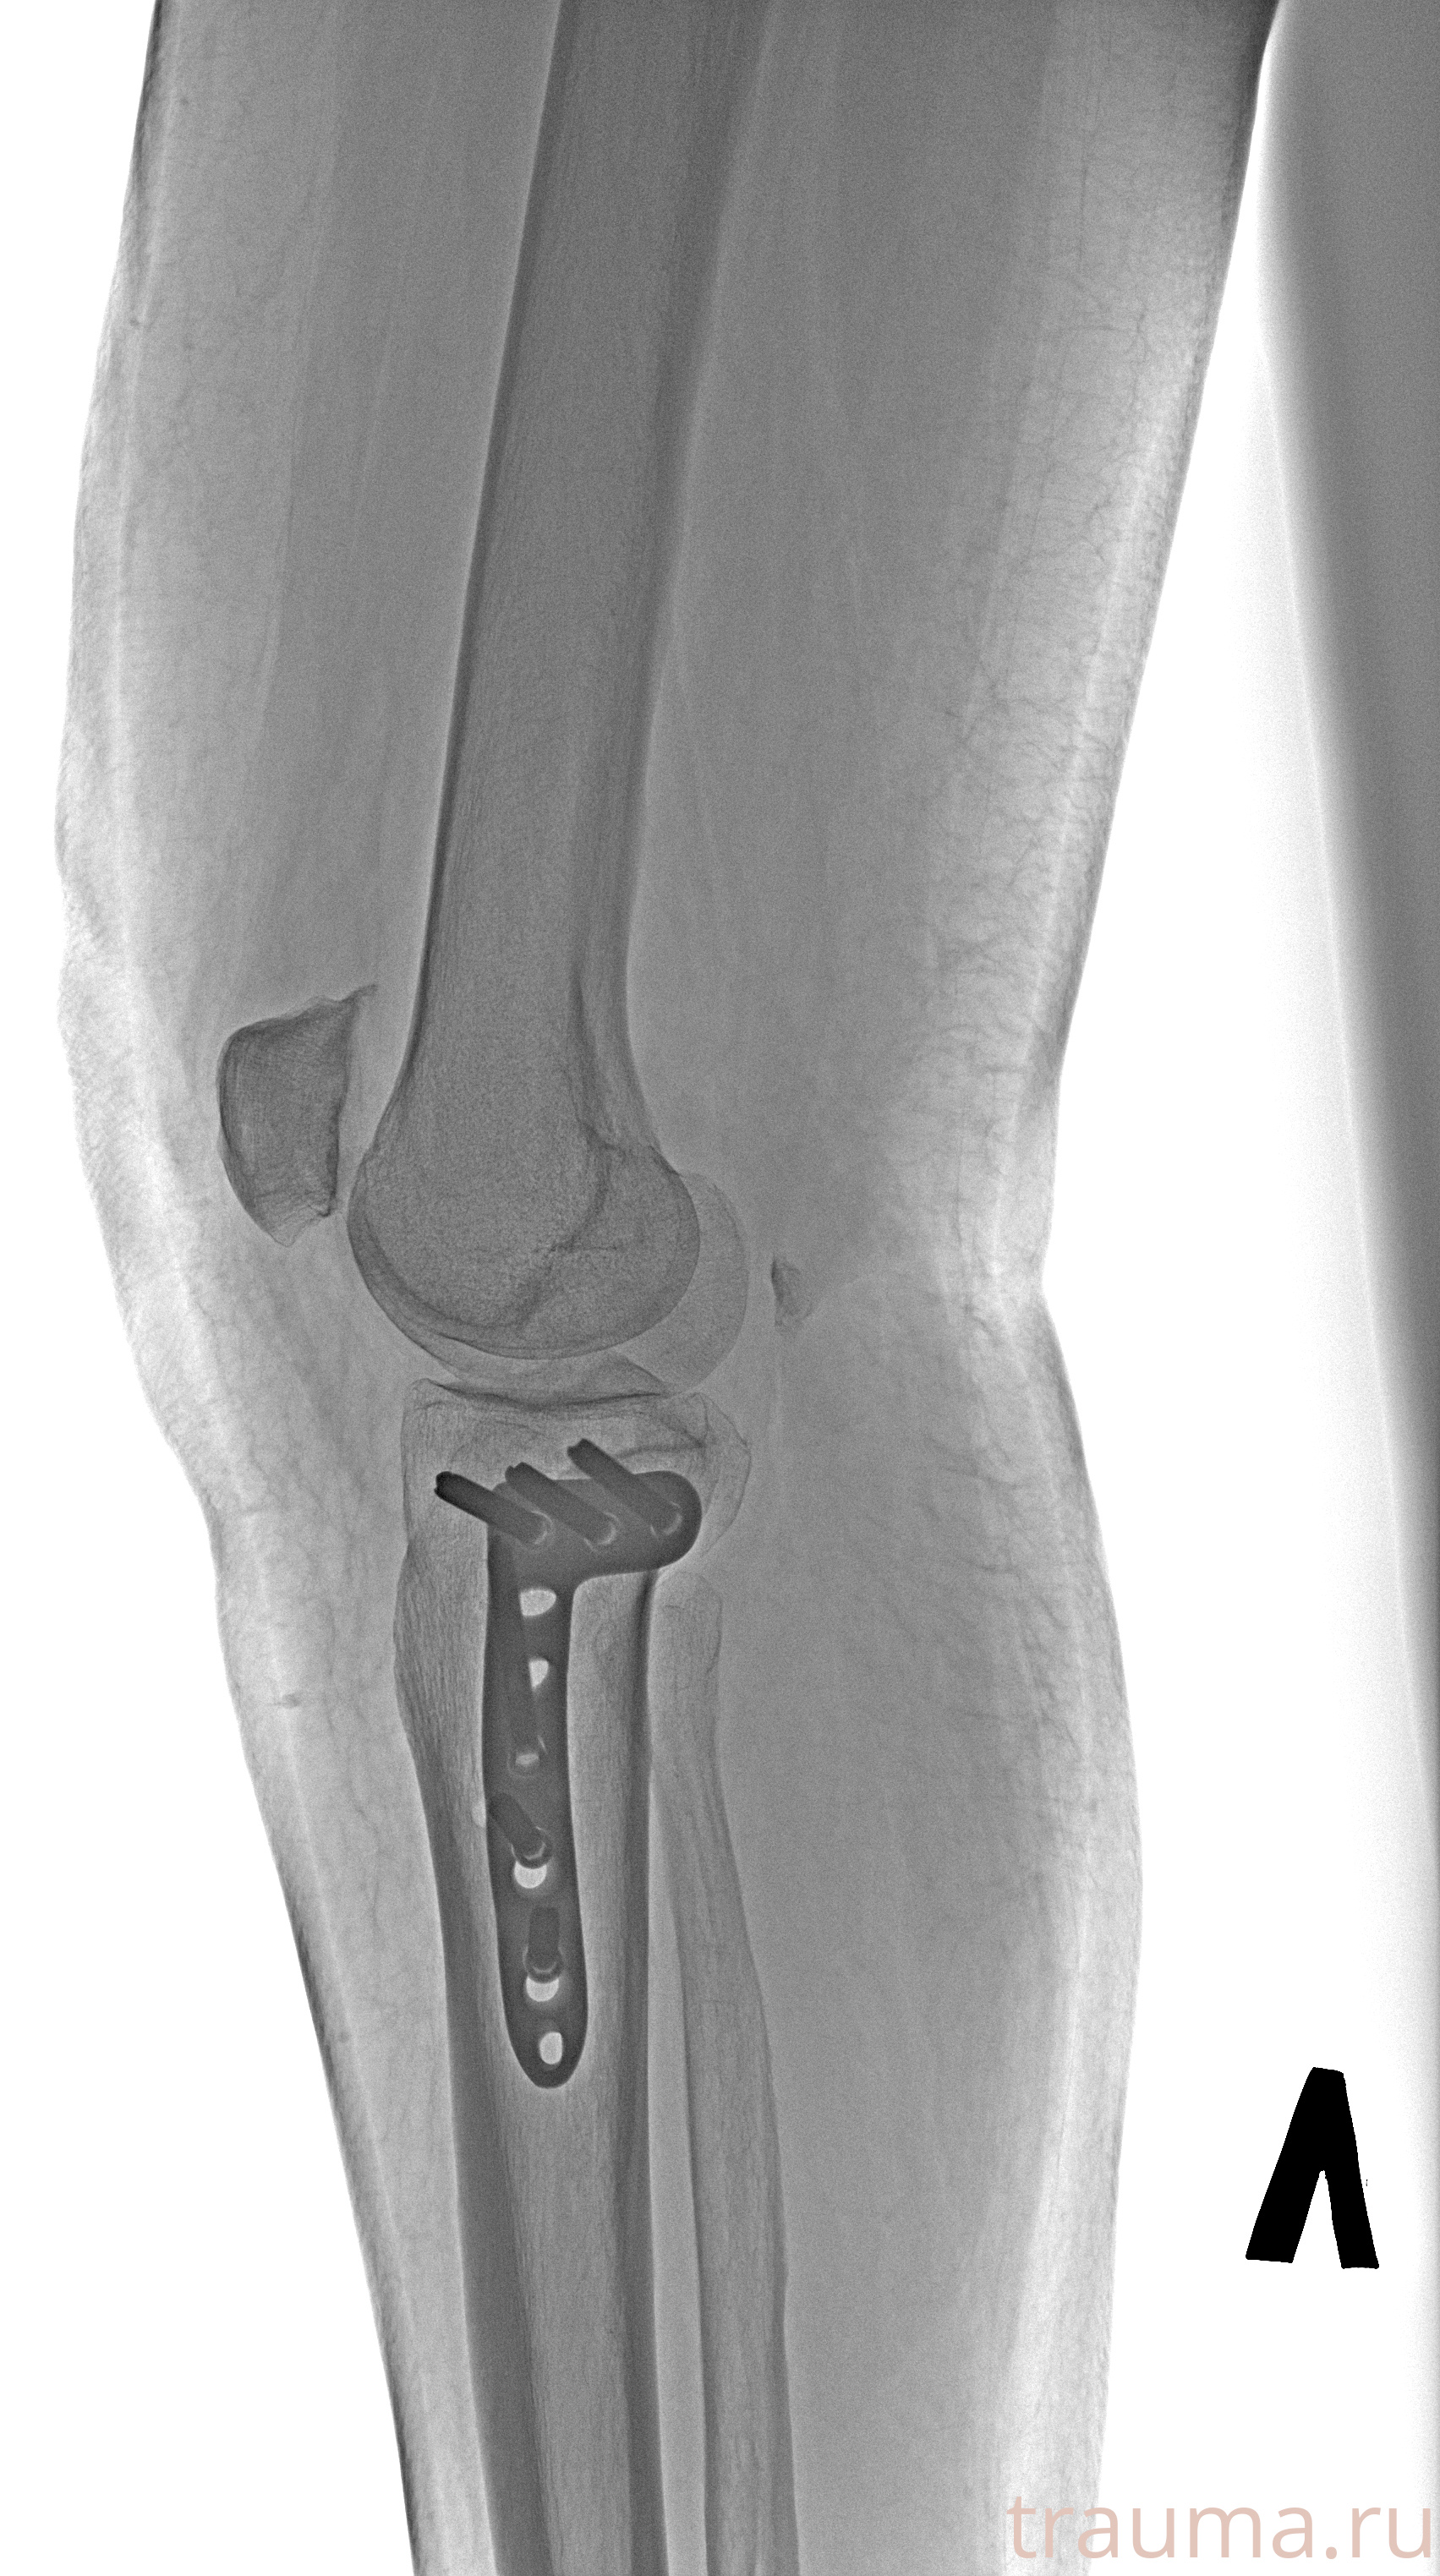

Рентгенограммы

Рентген на дому: по вашему адресу приезжает врач-рентгенолог, травматолог-ортопед с мобильным рентгеновским аппаратом, проводит диагностику травмы или заболевания, делает необходимые рентгенограммы, дает рекомендации по дальнейшему лечению. Получить качественные снимки в домашних условиях возможно благодаря уникальной методике, разработанной МосРентген Центром для института  Склифосовского